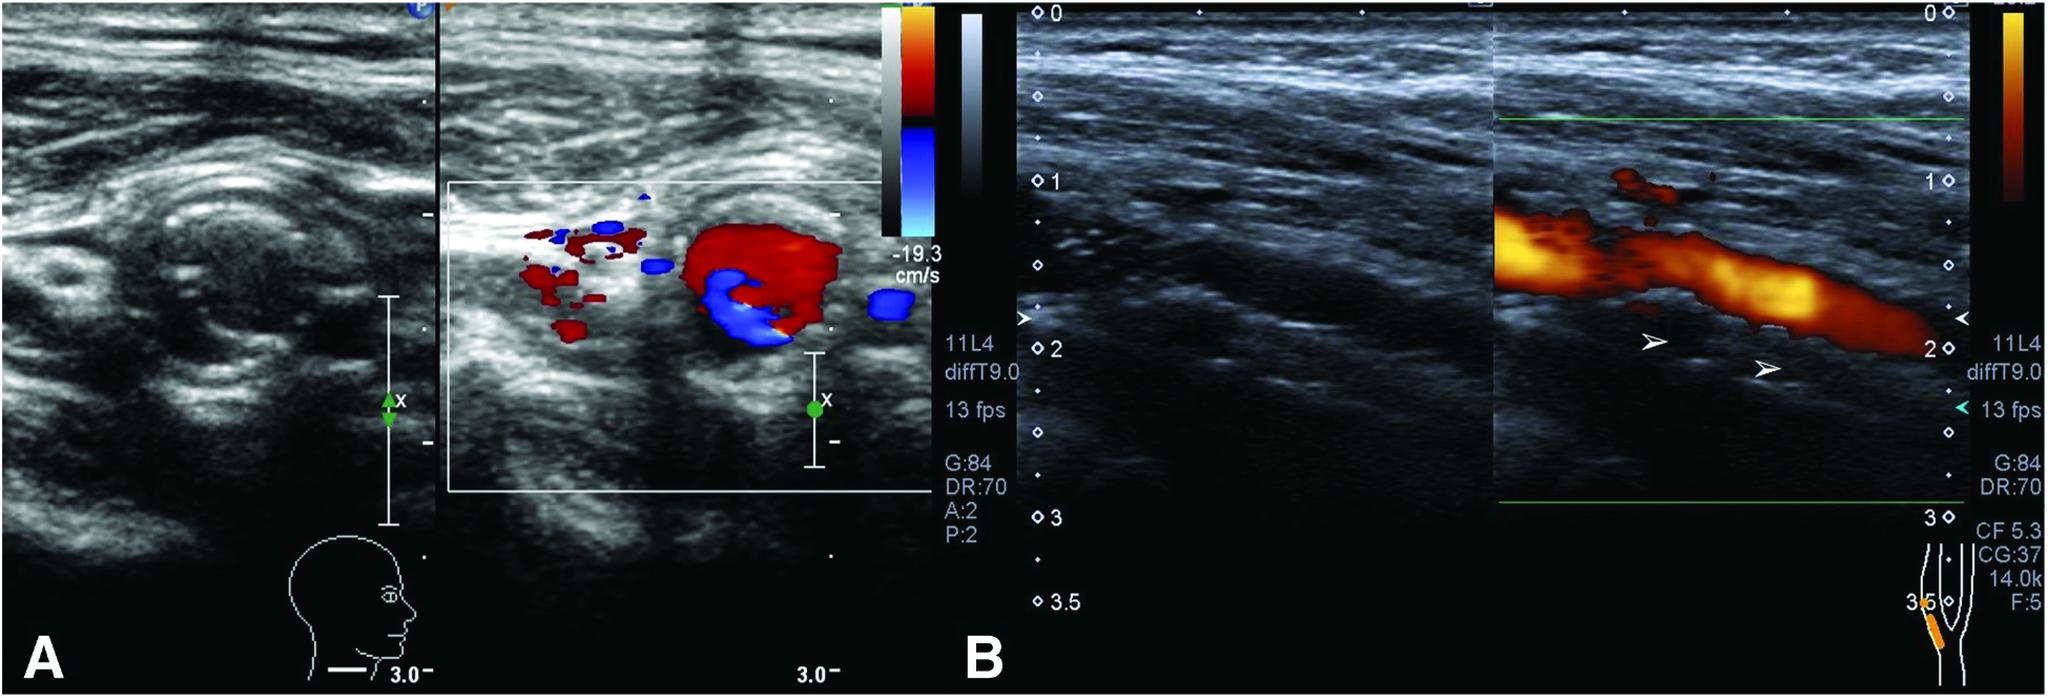

An 80-year-old man underwent carotid artery stenting (CAS) with an open-cell stent to treat asymptomatic right internal carotid artery (ICA) stenosis. Type III stent fracture occurred during CAS. Six months later, in-stent stenosis progressed on DSA. Repeat CAS with a closed-cell stent was performed. CT showed expansion of the narrowed lumen. The patient remained stroke-free and carotid artery restenosis did not occur for 3 years postoperatively.

一名80岁男性接受了使用开放式支架的颈动脉支架置入术(CAS),以治疗无症状的右侧颈内动脉(ICA)狭窄。在CAS过程中发生了III型支架断裂。6个月后,数字减影血管造影(DSA)显示支架内狭窄进展。遂使用闭合式支架重复进行CAS。CT显示狭窄管腔扩张。患者术后3年未发生中风且未出现颈动脉再狭窄。